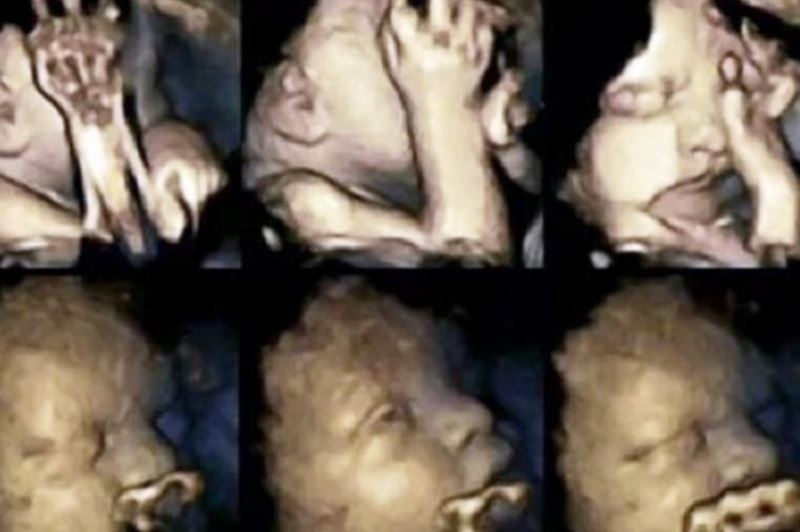

Εκεί είναι απαγορευτικό. Δεκάδες έρευνες έχουν γίνει σχετικά με το αν επιτρέπεται το κάπνισμα κατά τη διάρκεια της κύησης. Μία νέα μελέτη όμως, έρχεται να δώσει την απάντησή της με ένα βίντεο. Επιστήμονες στη Βρετανία θέλουν να δείξουν στις έγκυες που καπνίζουν συστηματικά πώς αντιδρά το έμβρυο στις ουσίες του τσιγάρου μέσα από τη μήτρα.